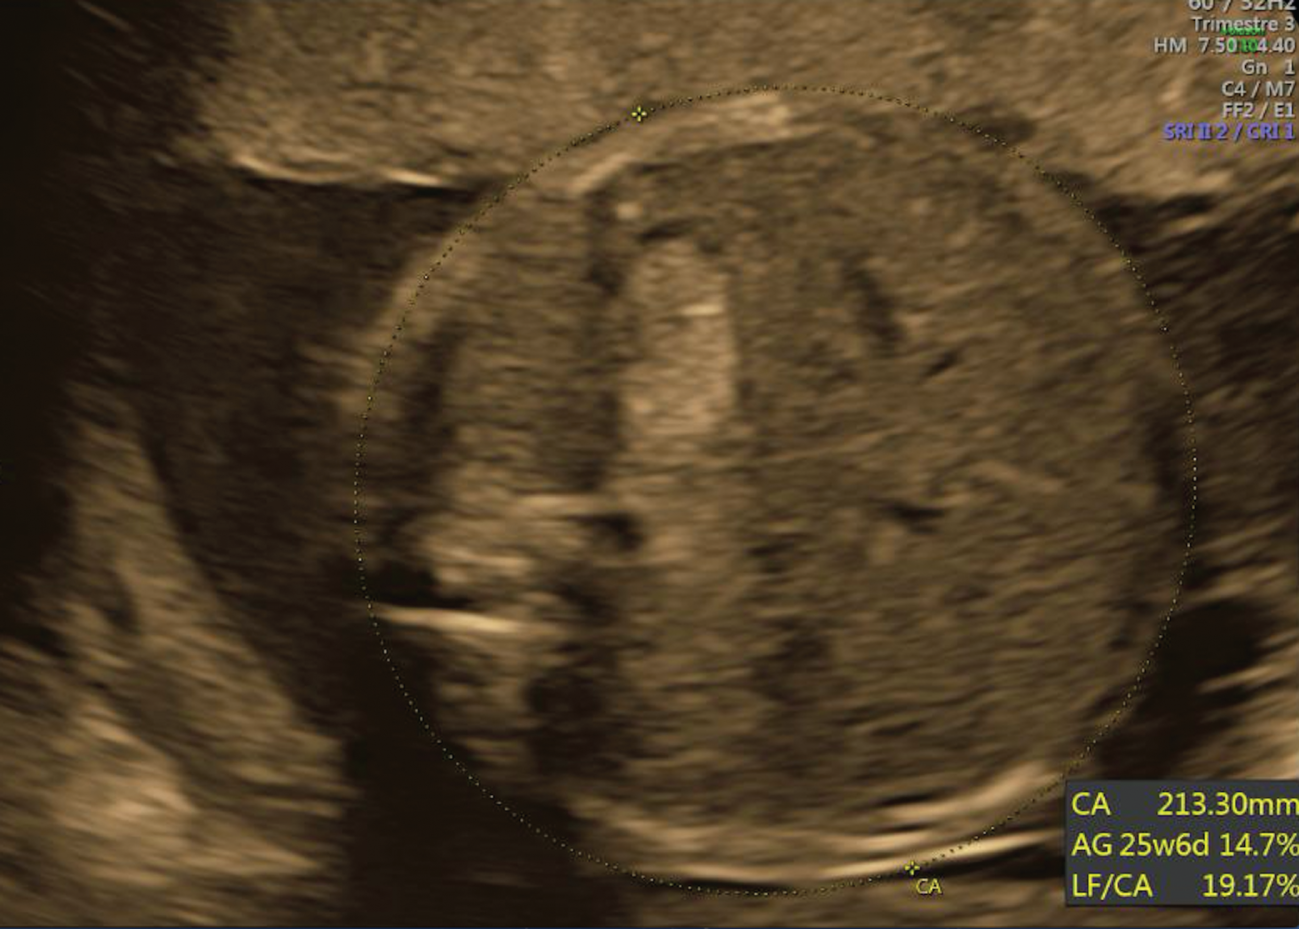

After a normal first trimester ultrasound, a 20-year-old primigravida woman was diagnosed at 27 weeks of gestational age (GA) with fetal growth restriction (FGR). The estimated fetal weight was at the 0.7th percentile. The fetus had facial dysmorphism with the mouth constantly open as an eclabium, hypoplastic nose (Figure 1), intragastric hyperechoic content (Figure 2) and skin scaling with skin particles floating in the amniotic liquid (Figure 3). The amniotic liquid was slightly hyperechoic with sedimentation of skin scales observed by vaginal ultrasound (Figure 4). No visceral abnormality was found. The amniocentesis performed showed an alpha-fetoprotein increased ten-fold (60,500 μg/L). Those findings recall a severe congenital ichthyosis and termination of pregnancy was proposed, but refused. Within several weeks we observed progressively fetal immobilism and hydramnios. At 30 weeks of GA corticosteroids prophylaxis and tocolytics were administrated to prevent premature delivery secondary to uterine contractions due to hydramnios. At 31 weeks of GA the patient gave birth to a baby boy of 1380 g, 40 cm of height and 28 cm of cranial circumference and normal cord blood pH. The Apgar score was 3–3–3. The baby boy had severe ichthyosis, atrophic ears, everted eyelids (ectropion), a hypoplastic nose, eclabium and stiffened skin surface. The couple opted for palliative care and the baby died at 33 min of life. An autopsy was refused. Comparative genomic hybridisation (CGH) array and clinical exome on cord blood were negative.

Intragastric hyperechoic image.

We want to underline the presence in our case of an intragastric hyperechoic image, reflection of the skin scales swallowed by the fetus, which is a feature only described once to the best of our knowledge [12]. We consider this as a rare sign that in the presence of other sonographic features could potentially help sonographers in the prenatal diagnosis of congenital ichthyosis.